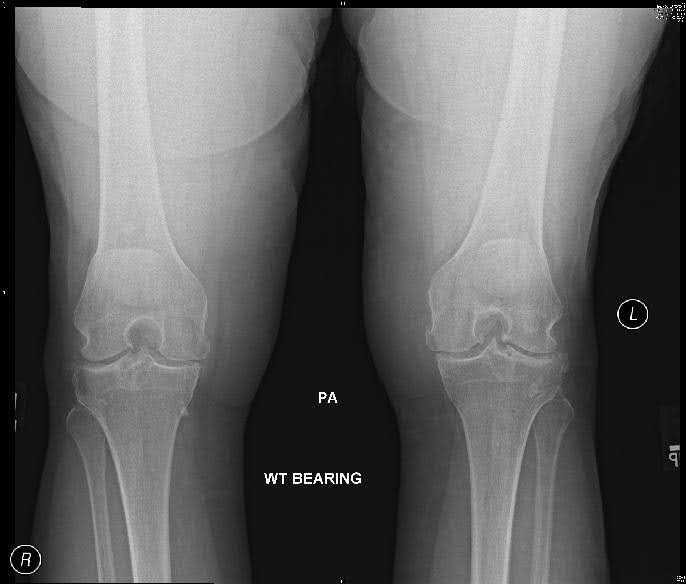

AP weight-bearing views including bilateral knees, lateral, and sunrise views are necessary to assess knee osteoarthritis radiographically. The critical findings of knee osteoarthritis on radiologic exam are as follows:2

- Joint space narrowing

- Osteophytes

- Subchondral sclerosis

- Subchondral cysts

- Loss of bone stock

- Malalignment

- Varus or valgus deformity

Finding osteophytes on x-ray best differentiates osteoarthritis from rheumatoid and other arthritides. A sensitive and specific criteria for knee osteoarthritis is the combination of knee pain, radiologic appearance of osteophytes and one or more of the following: age over 50 years, morning stiffness less than 30 minutes, or crepitus on active motion.

Bilateral weight-bearing views should be used to compare the affected with the unaffected side. Osteoarthritis should be assessed in each of the three knee compartments: medial, lateral, and patellofemoral. It should be noted that as many as 30% of adults over 65 years will demonstrate radiographic appearance of osteoarthritis, but one-third of these individuals will be asymptomatic.3 Thus, it is important to correlate clinical and radiographic findings to reach a diagnosis of symptomatic knee osteoarthritis, a clinically relevant entity.

Pre-op X-Rays

Figure 1. Pre-op x-rays.